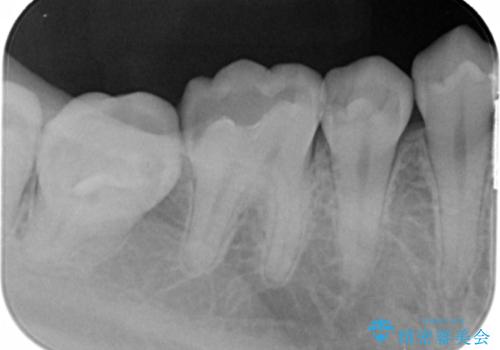

- 「久々の歯医者なの虫歯があれば全体的に治していきたい」とのことで来院。

虫歯の他にも不適合修復物が確認できましたが、「今回は虫歯がある箇所だけ」とのご希望があり該当箇所を治療していきました。

- 右上45 セラミックインレー 77000円×2本費用は治療当時の料金となります

今回は虫歯の治療のみのご希望であったため、掲載している写真の右側2本(口腔内の手前側)を治療していきました。